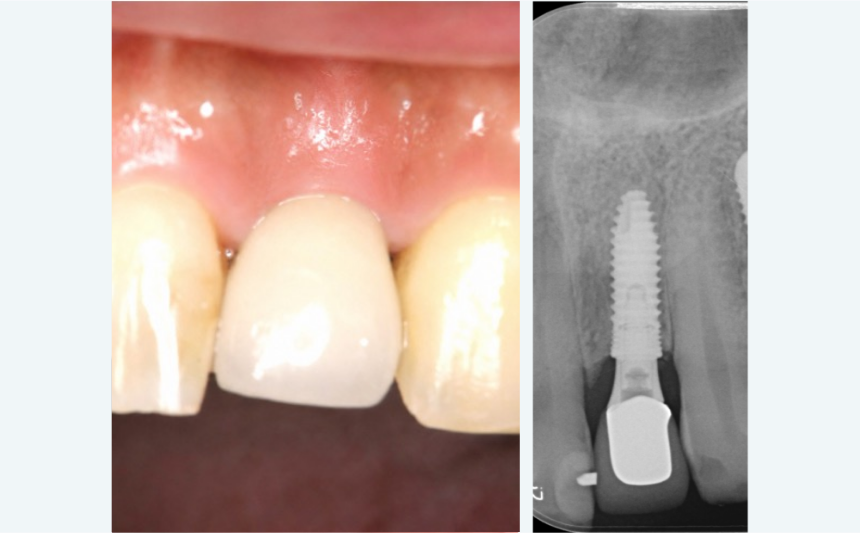

BEFORE

事故により前歯が破折。その後抜歯。

事故により前歯が破折。その後抜歯。

ブリッジだと削る量が多くなるため相談

ブリッジだと削る量が多くなるため相談

AFTER

違和感のない自然な前歯に

違和感のない自然な前歯に

自信を持って笑えるようになったと満足いただきました

自信を持って笑えるようになったと満足いただきました

| 治療内容 | 前歯1本のインプラント+ジルコニアクラウン |

|---|---|

| 治療期間 | 約6ヶ月 |

| 費用 | 約45万円(税込) |